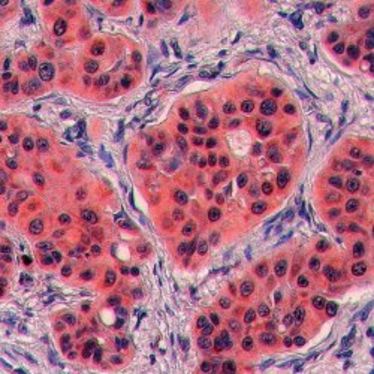

CeRA Seminar: Testis Cancer

CeRA Seminar: Testis Cancer